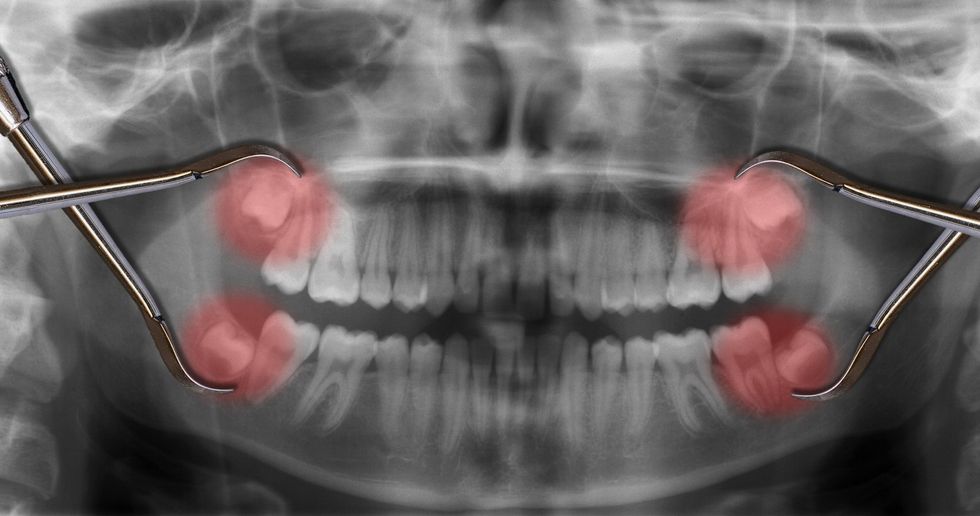

Dhëmballët janë të futura në majë dhe në fund të nofullës. Të rriturit shpesh kanë 4 dhëmballë. Mjekët këta dhëmbë i kanë shpallur të panevojshëm, andaj shpesh i nxjerrim, transmeton Telegrafi.

Nxjerrja e tyre megjithatë mund të ketë pasoja. Për shkak të lidhshmërisë së gojës dhe pjesëve të tjera të trupit, disa njerëz ndiejnë shtangim të përhershëm pas operacionit.

Nxjerrja e paarsyeshme e tyre mund të shkaktojë infeksione, deri te lëndimi i nervave të fytyrës, dhembje, gjakrrjedhje të pakontrolluar dhe gjithsesi shërim të gjatë.

Për shkak të këtyre simptomave, nxjerrjen e dhëmballëve kur nuk është e nevojshme nuk e rekomandojnë stomatologët. Ata thonë që më së miri është të pritet që të shfaqet problemi, sepse te shumica kurrfarë problemi nuk shfaqet.

Ekspertë mjekësorë kanë konstatuar që numri i intervenimeve kirurgjikale është zvogëluar për 60%. Pra, më shumë se gjysma e operacioneve të nxjerrjes së dhëmballëve vërtet është e panevojshme!